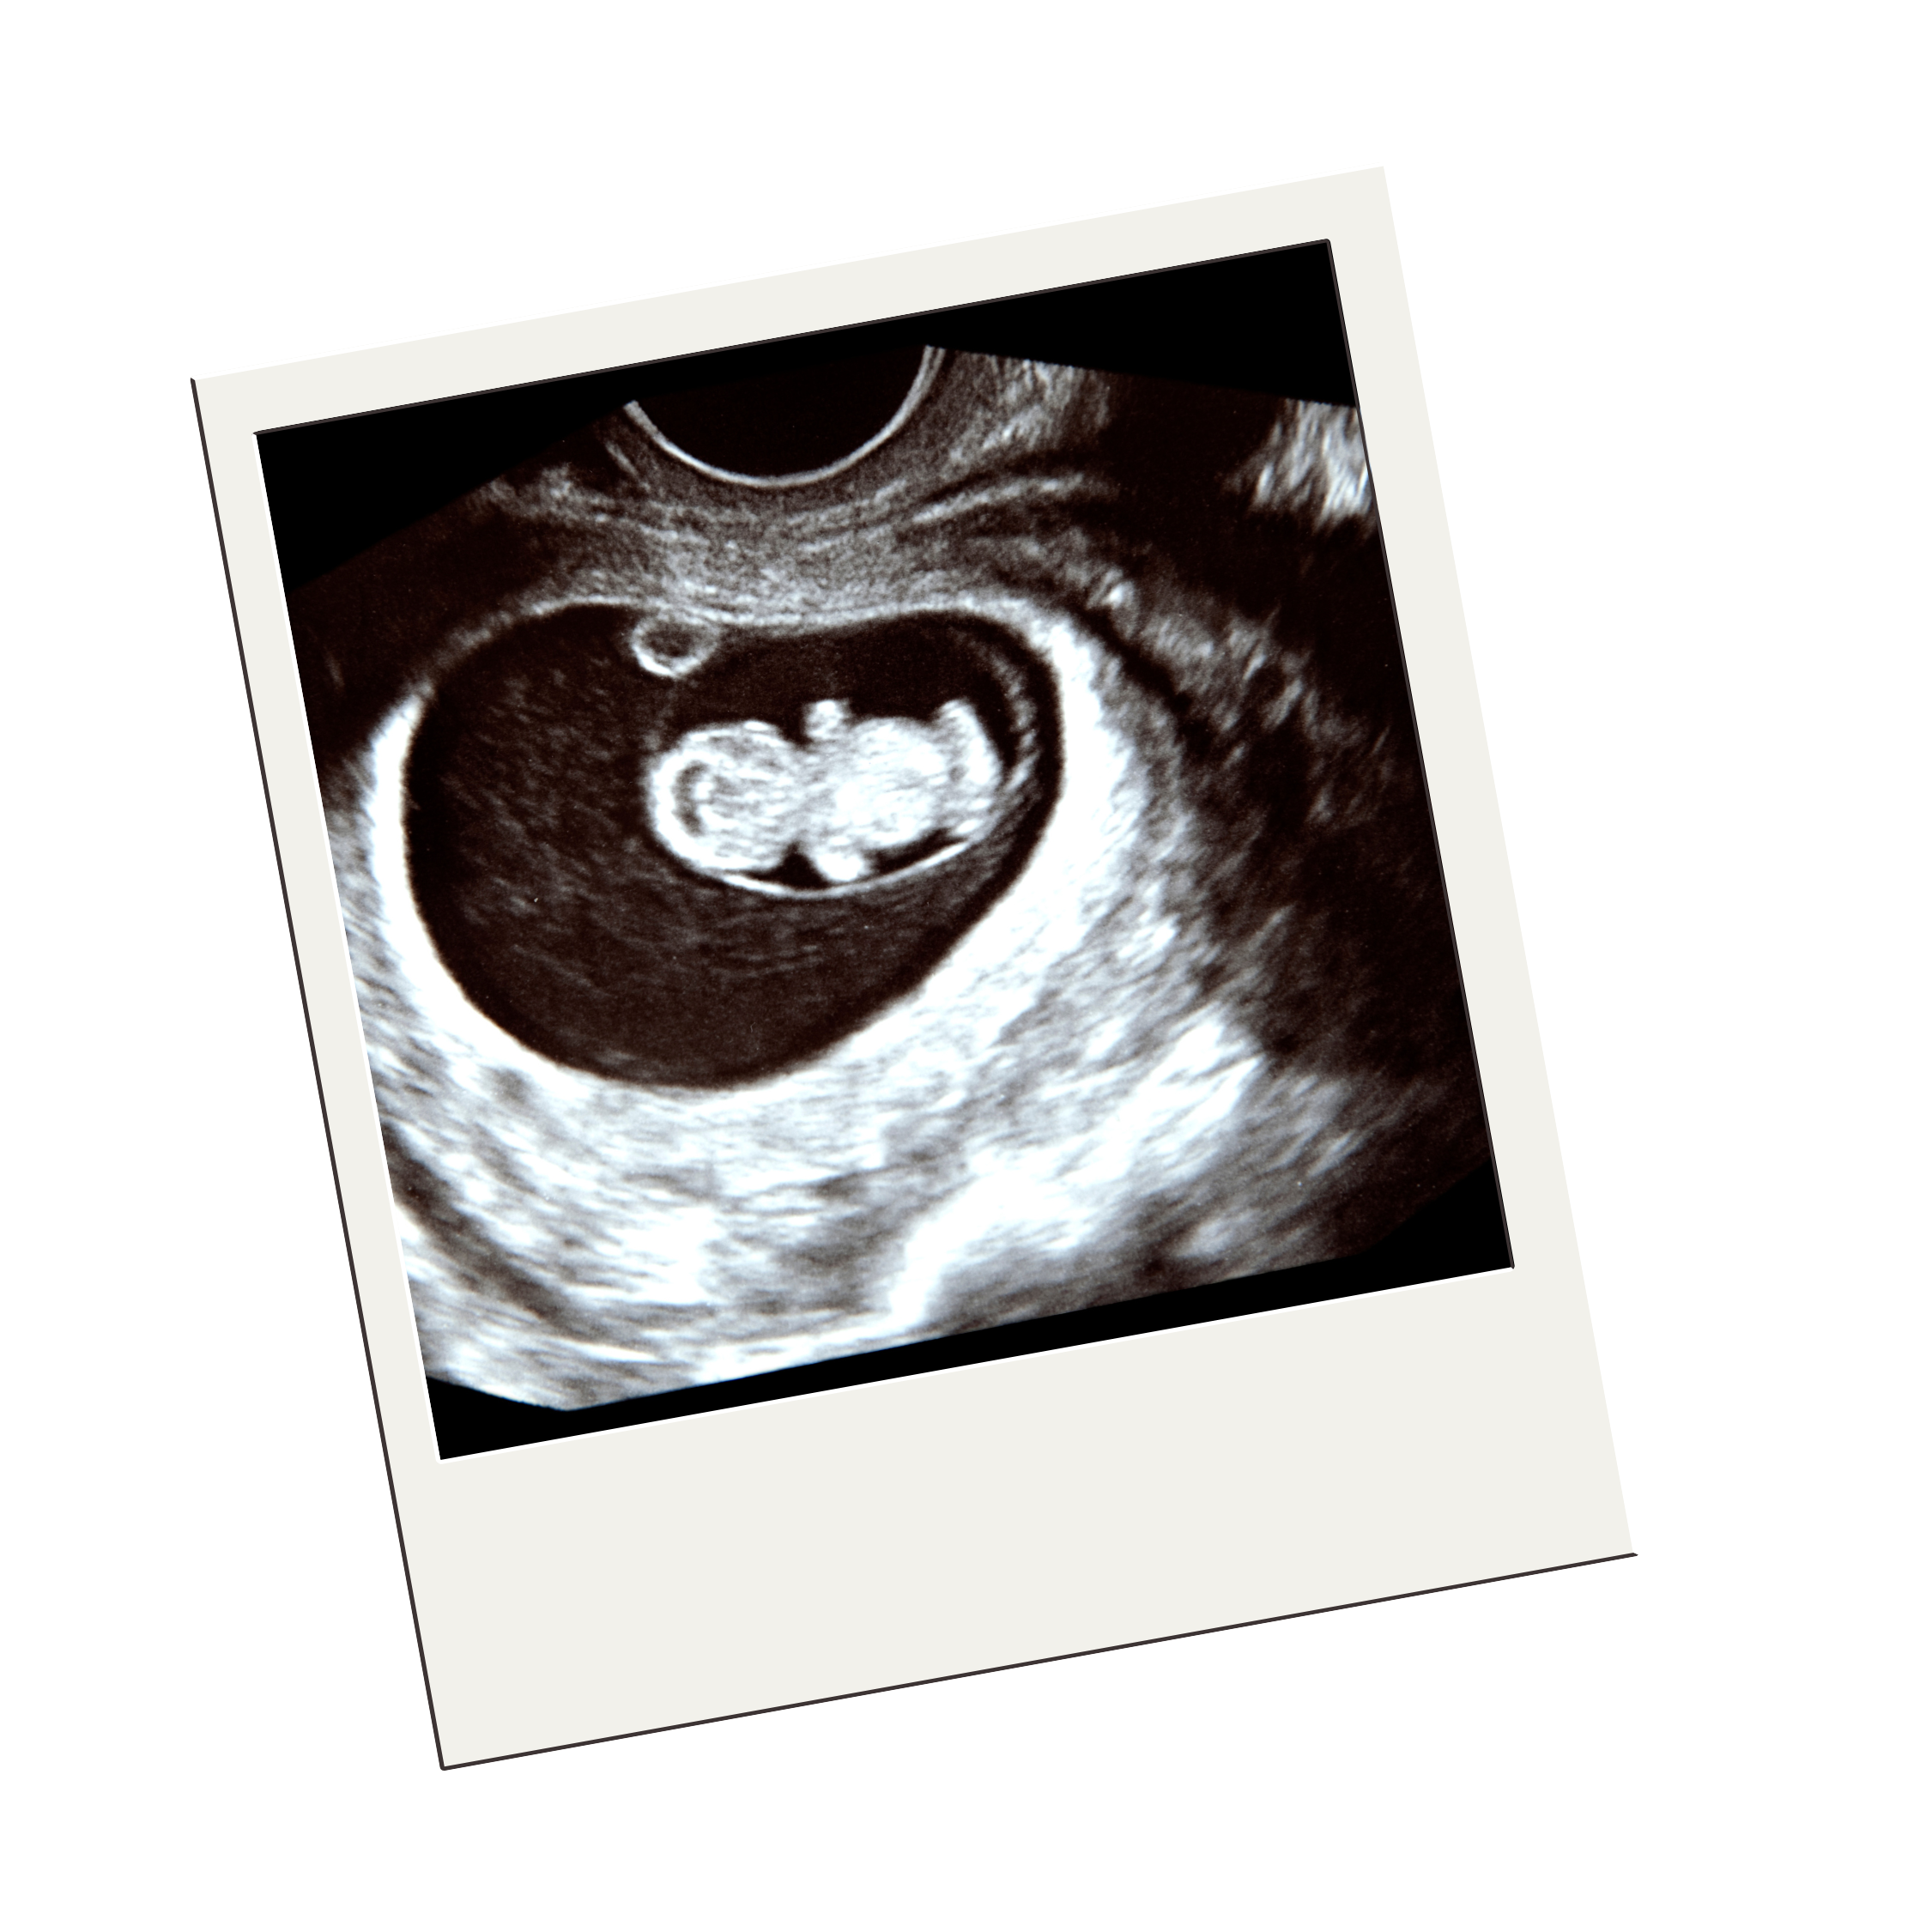

Early Pregnancy and Dating Scan

An early pregnancy scan, also known as a dating scan, is a type of ultrasound performed between 6 and 13 weeks of pregnancy. It serves several purposes to ensure both the mother and baby are progressing well during the early stages of pregnancy.

• Monitors Baby’s Development – It assesses your baby’s growth, measures their size, and confirms their heartbeat. It also determines the baby’s position within the womb.

• Confirms Number of Babies – The scan verifies whether you’re carrying one baby or multiples (twins or more).